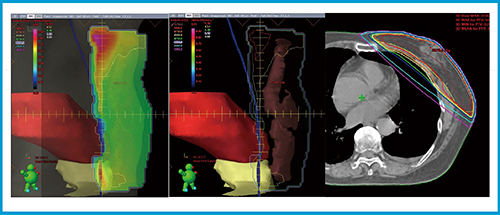

これまでのFFビームを使用した乳房接線照射においては,physical wedge法,FinF法共に体表外側までを均一に照射することにより,胸壁の呼吸性移動が生じても照射野から外れることなく照射できていたと考える。従来型リニアックによるFinF法を用いた乳房接線照射の線量分布を図1に示す。Halcyonによる乳房接線照射は図1の線量分布と同等,あるいはそれ以上に均一に照射することが望まれる。

図1 「CLINAC iX」(バリアン社製)によるFinF法の線量分布と各ビームのBeam’s Eye View

(2) 拡大した関心領域に対して最適化計算を行い,均一な分布を作成する(図3)。体表外側まで線量分布が作成されていることが確認できる。

図3 最適化計算用structure setでの最適化計算

左から最適化パラメータ,最適化によって得られたフルエンスマップ,その時の線量計算結果